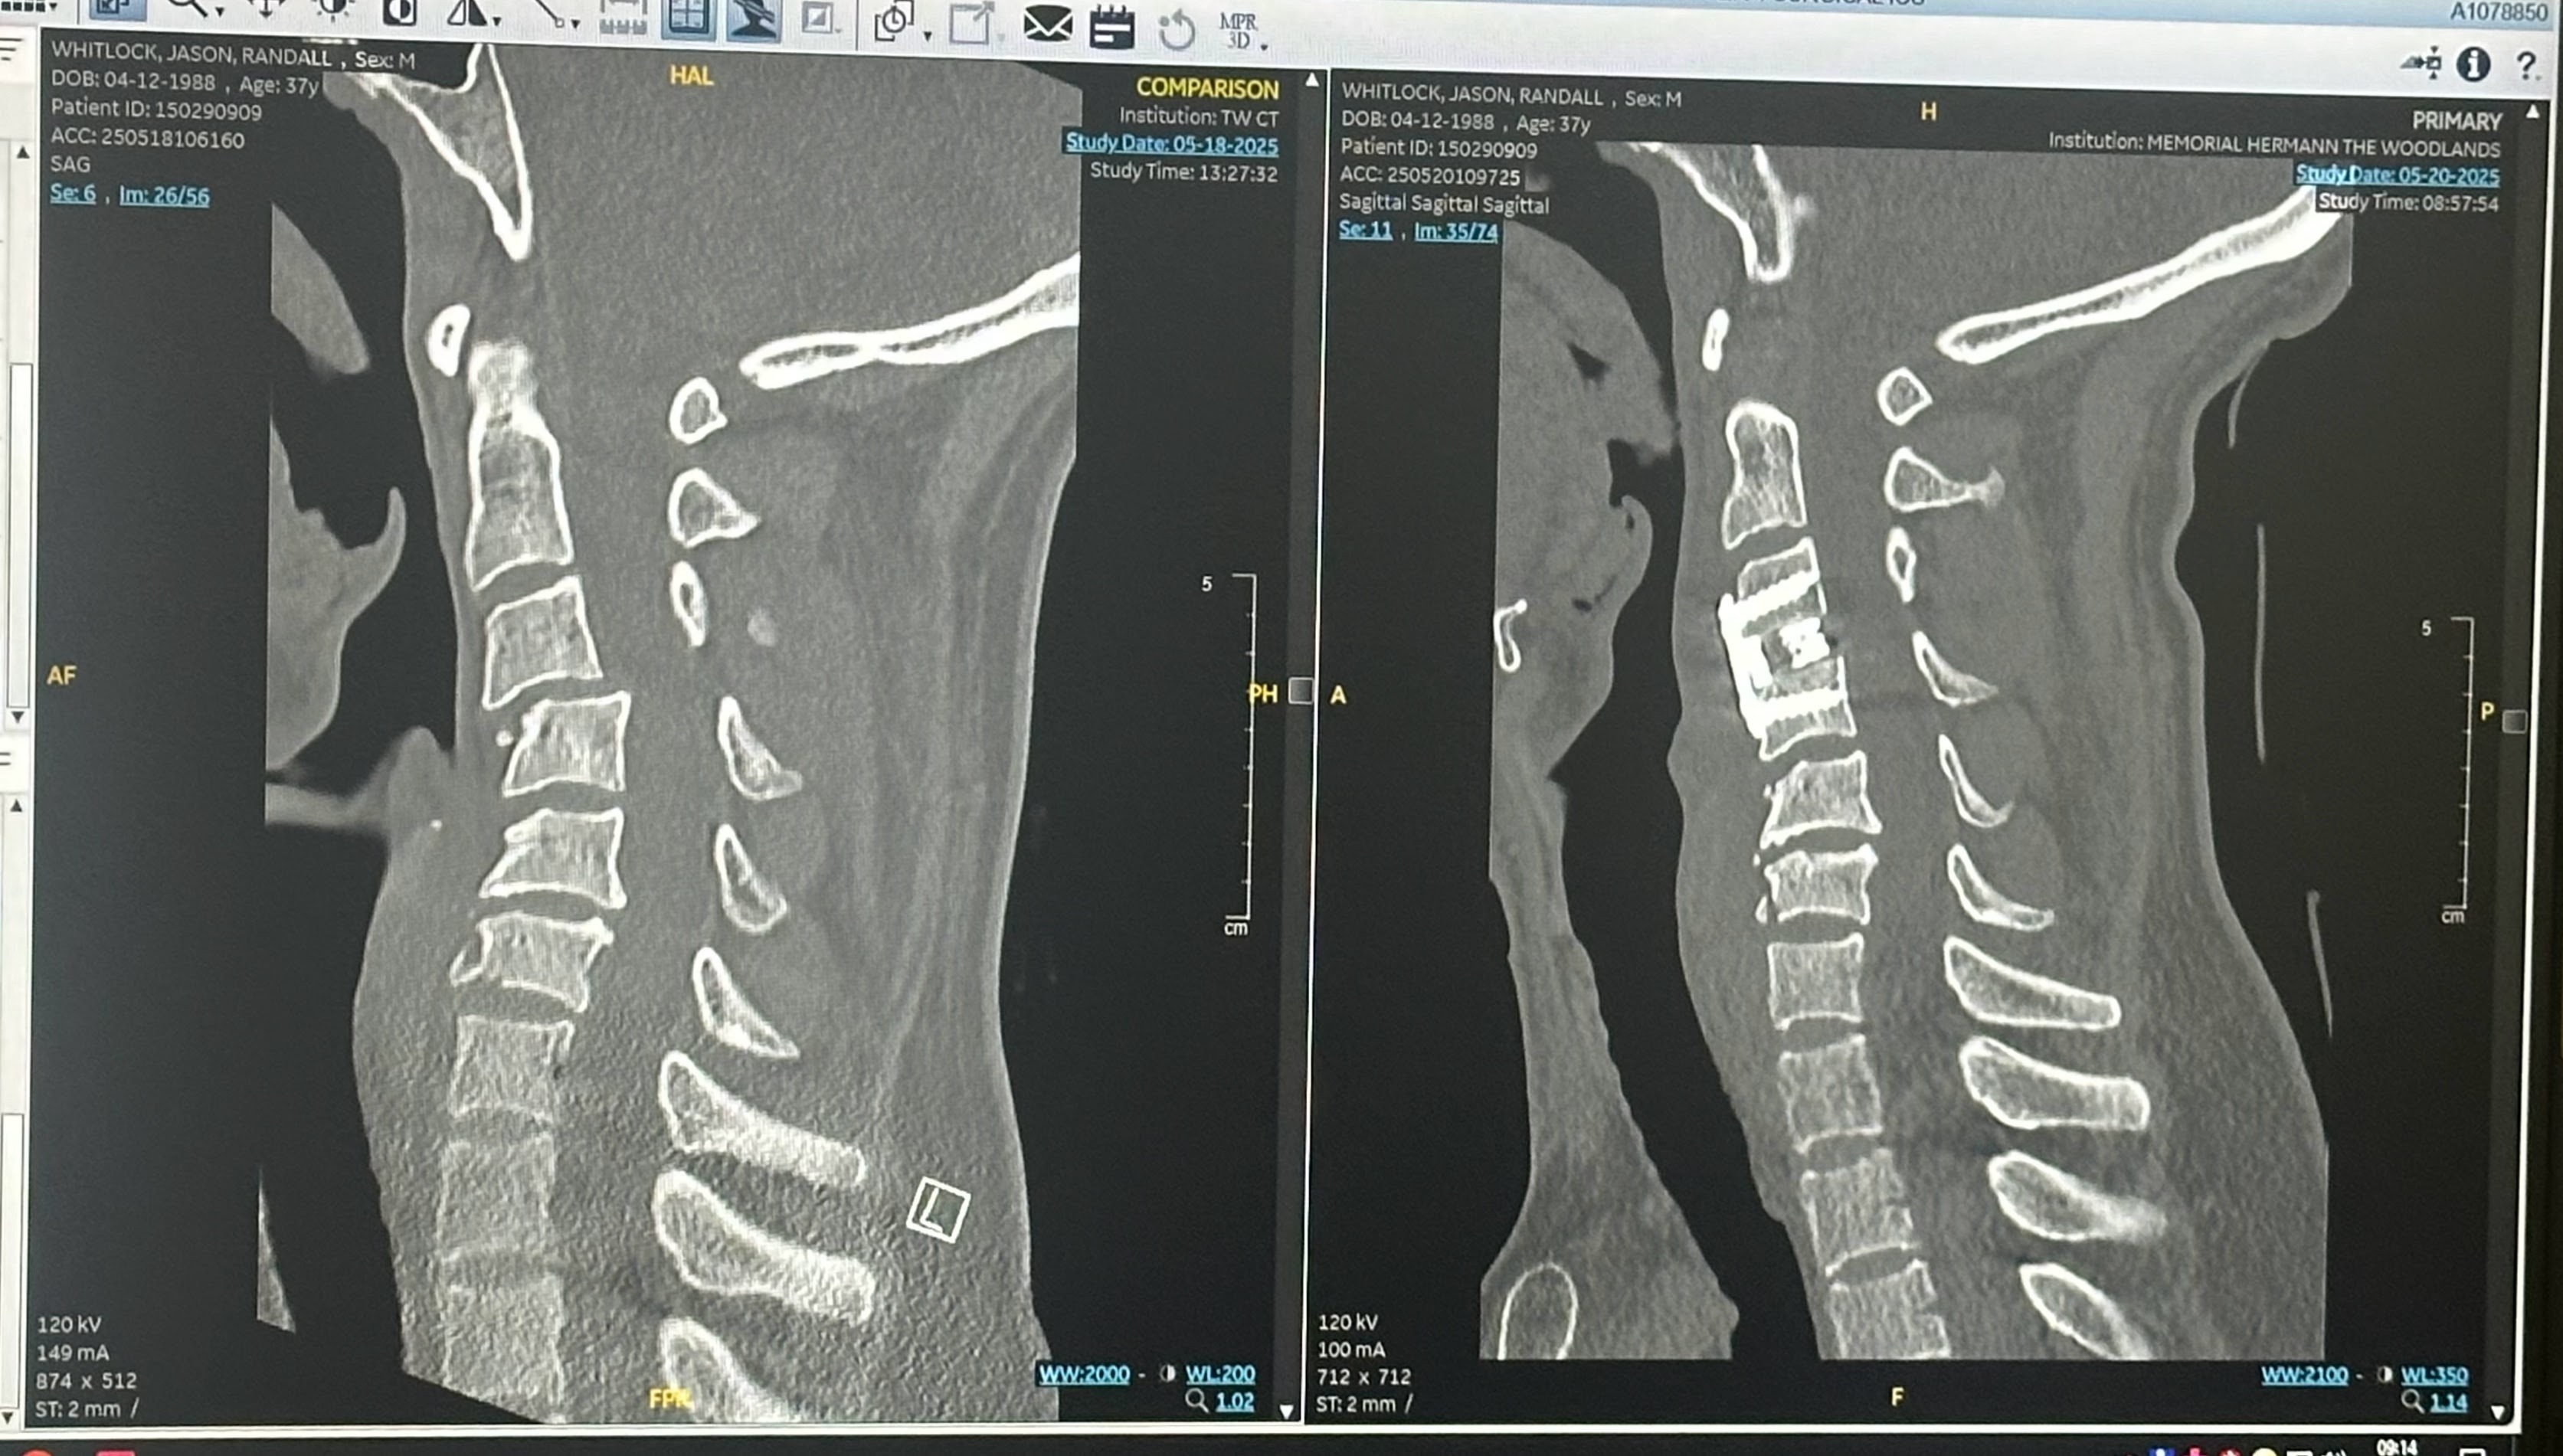

Hey everyone! I'm reaching out on behalf of my partner, Jason, who recently experienced a neck injury due to a recreational accident while we were visiting family out of town. He underwent emergency surgery to repair damage to his C3 vertebra along with a 4-day hospital stay. We are incredibly thankful that he retained full mobility and is expected to make a full recovery.